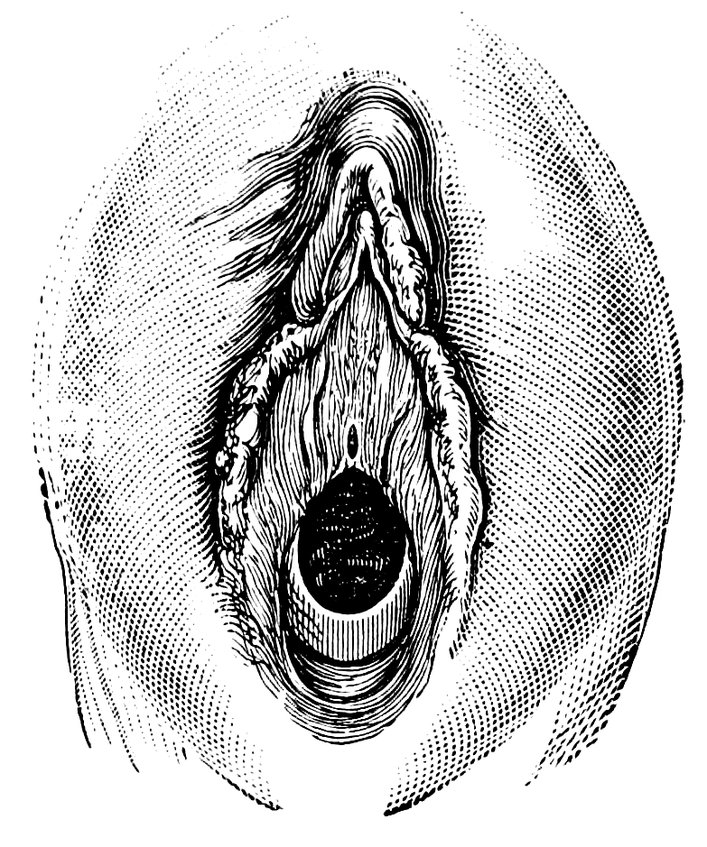

| 48. | The female pudendum, or vulva, with the labia majora | 204 |

| 49. | Vestibule of the vagina, with the labia minora or nymphæ, etc | 205 |

| 50. | The uterus, the left Fallopian tube and the left ovary, etc | 207 |

| 51. | Female internal genital organs in the fully developed state | 208 |